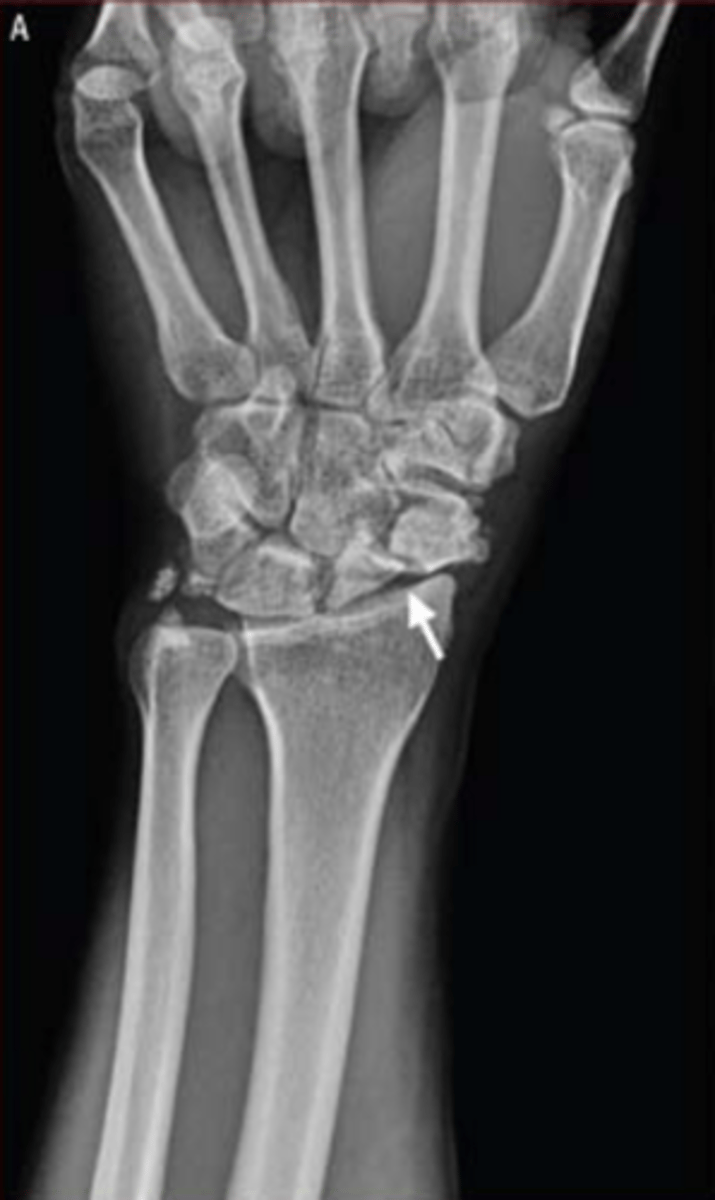

what radiograph view is this figure?

posteroanterior

what does the white arrow in the radiograph in this image indicate?

non-union scaphoid fracture